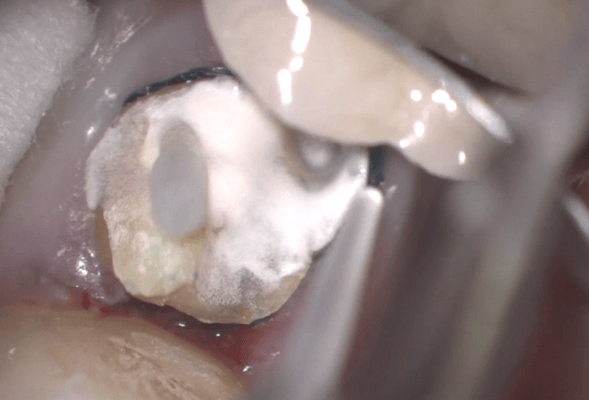

写真はすべてミラー像です。上顎左側側切歯遠心面の大きな虫歯です。エキスカで丁寧に軟化象牙質を除去していくと、歯髄腔まで本当に皮一枚になりました。血流が見えるようです。エキスカから伝わる組織の硬軟の感覚と対物-接眼レンズからの像が ”皮一枚”を達成できたと思います。皮一枚ですが、硬組織は残っていますので、ティース・プライマーを塗布し、スーパーボンド・ラジオオペークとバルクベースにて覆髄をしました。もちろん、1ケ月後の歯髄診でも陽性反応を示し、歯髄は生きています。

メタルインレー下にはレジンの覆髄が施されていましたが、接着しておらず、ポロリと取れました。これが、2次齲蝕(治療後の虫歯の再発)の原因です。多量の軟化象牙質(虫歯)を除去していくと、歯髄腔(神経と血管が入っている部屋)まで紙一枚。うっすら赤い血流も確認できます。齲蝕除去中に口蓋側の咬頭が破折しましたので、グラスファイバーポストによって、生活歯の支台築造。神経も取らずに残せる歯は、本当に多くあります。